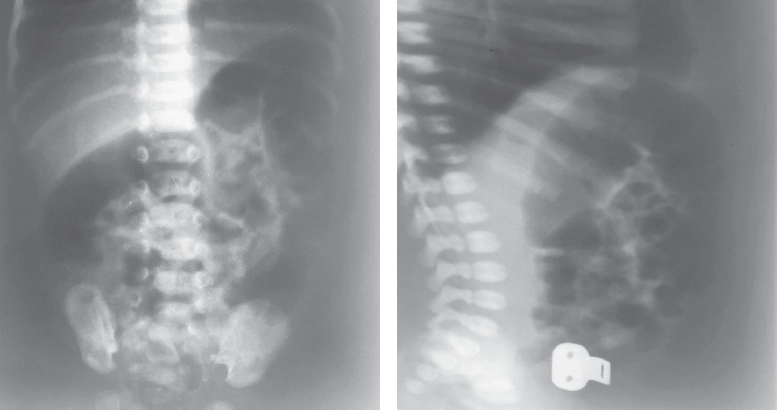

Доношенный полновесный ребенок поступил на 5-е сут жизни в стационар с жалобами на вздутие живота, срыгивания с примесью желчи и отсутствие стула. На обзорной рентгенограмме брюшной полости выявлено равномерное распределение газа по кишечнику без уровней жидкости и раздутая на всем протяжении газом толстая кишка (рис. 1, 2).

Рис. 1. Обзорная рентгенограмма брюшной полости

Fig. 1. Plain abdominal X-ray

Ярким примером недооценки клинической картины служит случай 1. Отсутствие ярких симптомов кишечной непроходимости и эффективность очистительной клизмы позволили уже в первые дни жизни исключить у ребенка хирургическую патологию. Травматичные роды и использование вакуум-экстракции для родоразрешения стали основой для ошибочной интерпретации его состояния. Пациент наблюдался как ребенок с парезом кишечника на фоне черепно-спинальной травмы. На обзорной рентгенограмме брюшной полости расширение толстой кишки на всем протяжении было недооценено. Наличие «светлого» промежутка, характеризующегося отхождением стула, полностью исключило какие-либо подозрения на хирургическую патологию. Ребенок был выписан на амбулаторное лечение педиатром без рекомендации дальнейшего наблюдения хирургом. Следует отметить, что подозрение на кишечную непроходимость, задержку отхождения мекония и расширение толстой кишки при рентгенологическом исследовании у детей первых дней жизни должны наводить неонатолога и тем более хирурга на мысль о возможности болезни Гиршпрунга. В подобных случаях целесообразно выполнять ирригоскопию, которая позволит установить правильный диагноз в большинстве случаев.